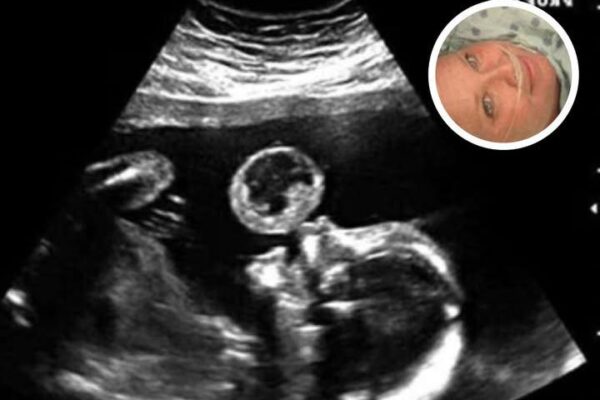

61-year-old woman who claimed to be pregnant with a 21-year-old boy is..

A recent online story involving a 61-year-old woman who claimed she was pregnant with the child of a 21-year-old man has drawn intense attention across social media and digital news platforms. What began as a surprising personal announcement quickly escalated into a public debate that blended curiosity, skepticism, and concern, highlighting how rapidly unverified claims…